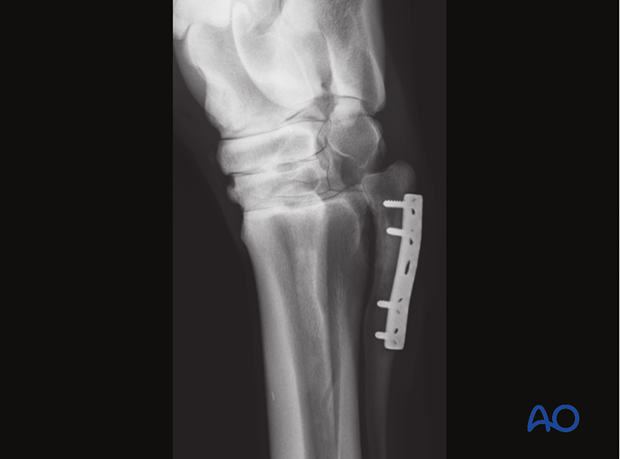

Completed fixation

Occasionally, one cannot achieve sufficient stability with screws placed in the splint bones only. In such cases inclusion of the palmaro/plantaro-lateral/medial cortex of the third metacarpal/metatarsal bone in the fixation should be considered.

It must be kept in mind, that this eliminates normal micro movement within the joint and between the splint bone and the third metacarpal/metatarsal bone.

If the proximal part of the splint bone is not firmly attached to the third metacarpal/metatarsal bone and/or is very short, there is a high risk of dislocation. In such cases, fixation of the proximal stump to the third metacarpal/metatarsal bone can represent a good option to achieve a stable fixation.